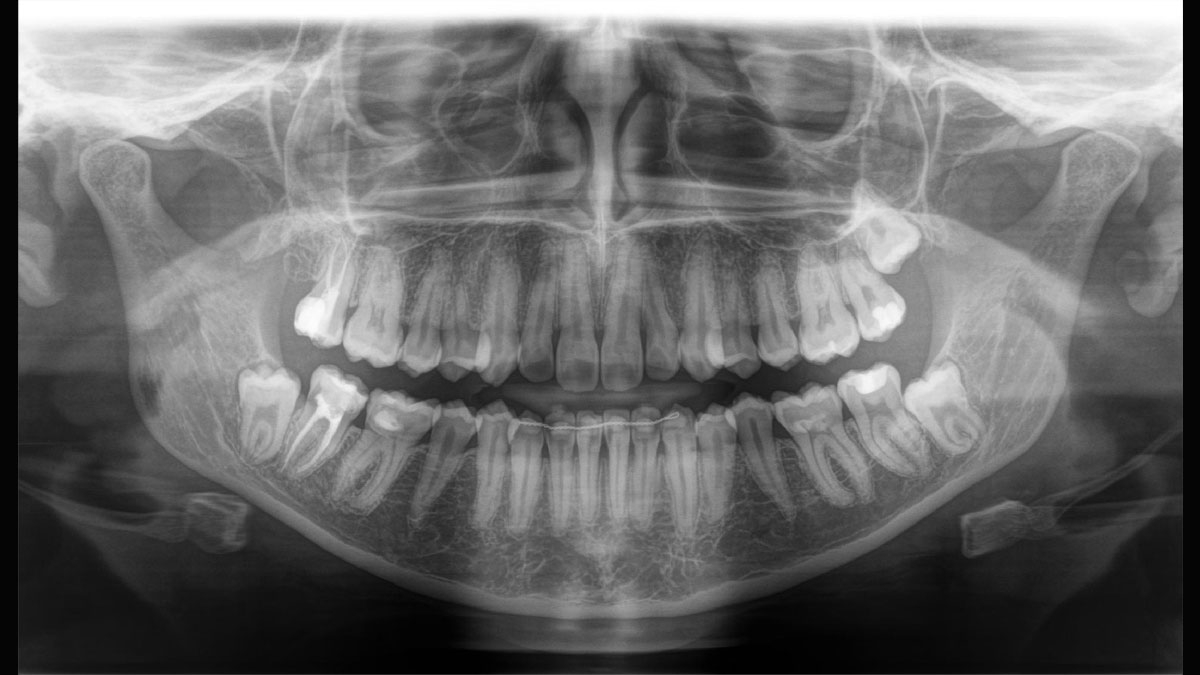

PIA (Patient Positioning & Image Assistant) je 10bodový koncept pro snadné polohování pacienta a rentgenové zobrazování a je především o dvou věcech: vysoké kvalitě snímků a komfortu pro pacienta a obsluhu rentgenu. PIA poskytuje podporu a zajišťuje nástroje pro zhotovení vysoce kvalitních snímků, potřebných pro analýzu léčby. Je zaměřen na ergonomii a komfort pacienta i obsluhy rentgenu. Patentovaný skusový blok automaticky zajistí správné naklonění hlavy, umístění pacienta v okluzní rovině, a spolu s 3bodovou fixací hlavy a pevnými madly pro stabilní polohu pacienta omezuje potřebu nežádoucích korekčních skenů.